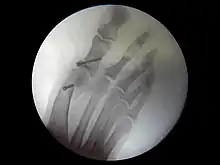

Du point de vue de la technique pure, l'opération peut être menée selon plusieurs modalités :

- chirurgie classique : le chirurgien incise la peau en regard des zones à traiter ;

- chirurgie mini-invasive[7] : les techniques sont adaptés pour permettre d'effectuer les mêmes gestes, mais par des incisions (et donc des cicatrices) plus petites et en préservant mieux les tissus sous-cutanés ;

- chirurgie percutanée[8] : les avancées techniques les plus récentes permettent de pratiquer les gestes chirurgicaux à travers la peau. La taille des incisions ne dépasse alors pas quelques millimètres.

Si les deux dernières s'accompagnent de suites opératoire plus simples pour les patients, toutes les techniques ne peuvent pas traiter toutes les déformations. C'est au chirurgien, entraîné à ces techniques modernes, d'opter pour l'une ou l'autre.